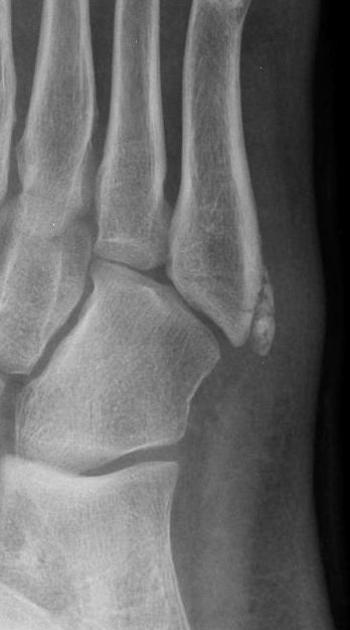

다음은 제5중족골 골절의 네 가지 방사선 영상이다. 손상은 무엇인가?

제5중족골 기저부 골절 (Fractures of the Fifth Metatarsal Base)

① 족저근막의 외측열 부착부의 견열 골절

② 단비골건 부착부의 견열 골절

③ 존스 골절(Jones fracture)

제5중족골 감입 골절(impaction fracture)로, 피로 골절으로 종종 시작된다.

④ 손상 부위 없음

이는 제5중족골 기저부의 정상적인 발달성 골돌기(apophysis)에 해당한다.

둘 다 발목의 회외 손상(supination injuries)으로 인한 견열 골절이지만, 전족부의 족저측이냐 족배측이냐의 구조에 따라서 어느 구조가 견열을 일으키느냐에 영향을 끼친다. 일반적으로 단비골건 견열 골절은 더 크고 관절내에서 발생한다. 존스 골절은 결절 조면의 약 1.5cm~2cm 정도 떨어진 곳에서 발생하며, 종종 피로 골절로 발전하는데, 대다수의 경우 수술적 치료가 요구된다. 발달성 골돌기(Developing apophysis)는 시상면 방향으로 된 성장판을 가지는데, 골화 중심이 종축 방향이기 때문이다.

△ 정상적인 발달성 골돌기 (Developing apophysis)